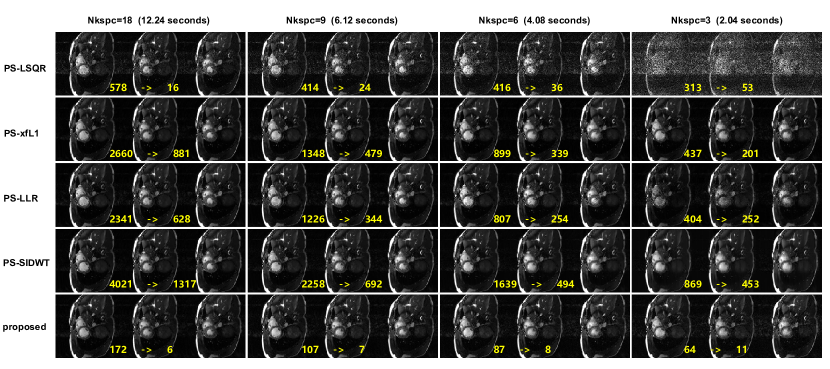

5.3 Prospective Experiments

The reconstructed images of one volunteer are shown in Figure 8. The results are consistent with the retrospective experiment, with only slight differences. Under Nkspc=18, all the regularized PS model algorithms have similarly good image quality. However, the image reconstructed by PS-LSQR method is obviously worse than other methods. When Nkspc is further reduced to 9 and 6, the performance of PS-LSQR deteriorates very quickly, while other methods can still maintain relatively good image quality. When Nkspc is reduced to 3, the images reconstructed by PS-LSQR are totally corrupted by noise, PS-LLR method becomes very unstable, the reconstructed images suffer from darkening artifacts. The images reconstructed by PS-SIDWT model are blurred at the blood-myocardium boundary. The images reconstructed by PS-xfL1 model and the proposed method have similar image quality. However, the proposed method is nearly 20-fold faster than the PS-xfL1 algorithm. The zoomed images of another volunteer are shown in Figure 9. The proposed method achieves good image quality and the fastest reconstruction speed simultaneously.